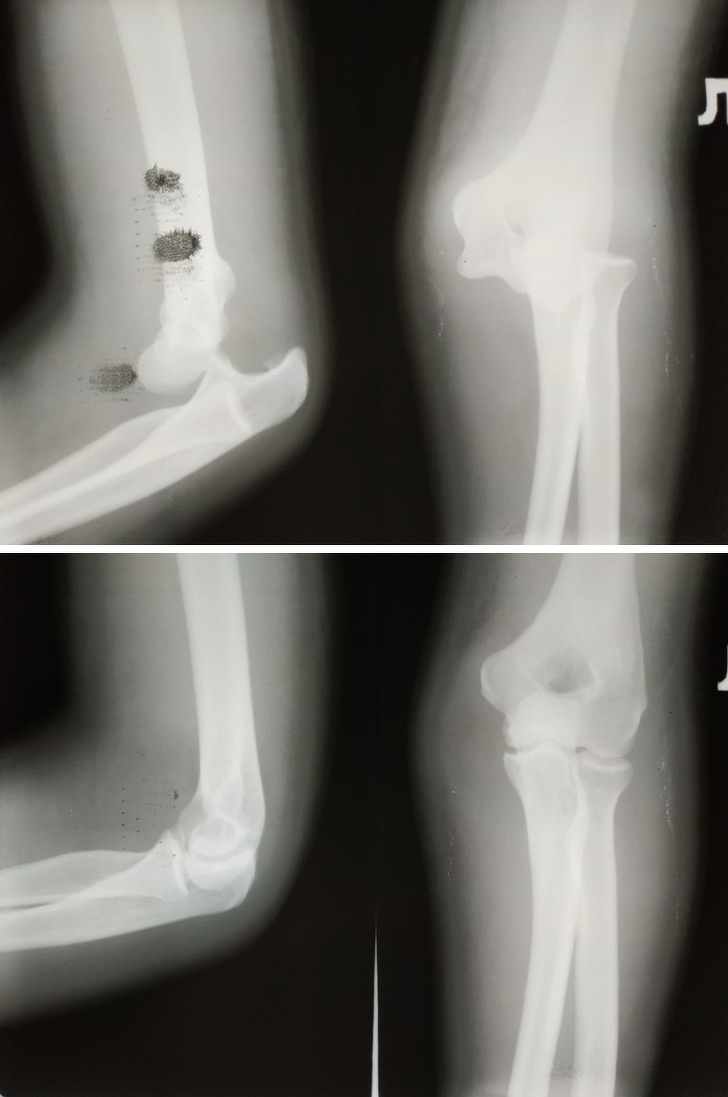

Вивих і здоровий суглоб